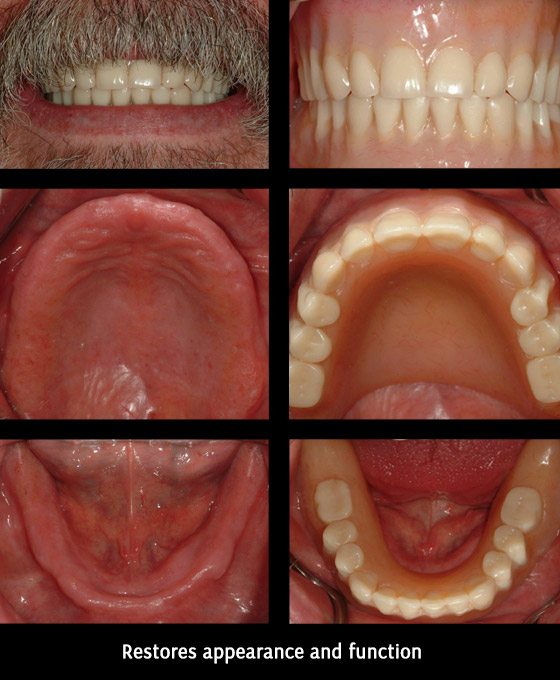

Before/ after treatment photos